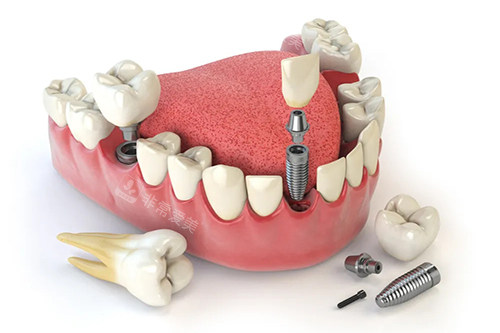

无论是常见的牙齿清洁、补牙,还是复杂的牙齿矫正、种植牙等项目,医生们都能够熟练操作,并且根据患者的具体情况制定个性化的治疗方案。

同时,清新口腔还不断引进新型的口腔诊疗技术和设备,如智能化口腔扫描仪、激光治疗设备等,为提高诊疗结果提供了有力的支持。